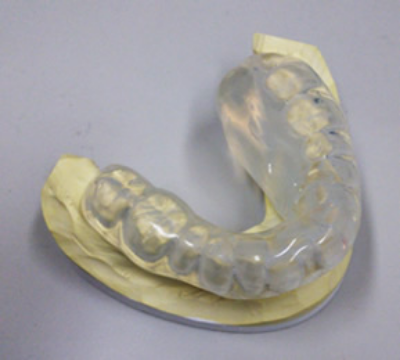

当院では頭頸部がんセンターの歯科医師、歯科技工士と協力し、密封小線源治療による重篤な副作用である顎の骨の炎症や壊死を予防するためのスペーサーと呼ばれるマウスピースを使用して治療を行っています。

早期の口唇がん、口腔がんに対する密封小線源治療5